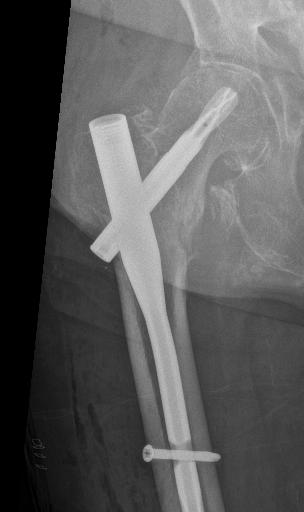

Osteosarkom i thorax som bedömdes som inoperabelt av thoraxkirurger. Dr Thomas Hilton och jag fixade det.

Den kanske viktigaste insatsen är nog ändå mitt arbete som klinisk mentor vid sarkomsektionen i Kapstaden. Jag hjälper till med operationer två dagar i veckan och har mottagning 1-2 dagar. Övrig tid använder jag till registerarbete. Då jag närvarar i den kliniska vardagen så kan jag bidra med min erfarenhet och får lära mig om de svårigheter och fattigdom som de flesta patienter lever i. Att bemästra smärtor, funktionsförlust och oro inför framtiden under sådana omständigheter är oerhört svårt. Hilton och jag har gjort den första van Ness rotationsplastik i Sydafrika som fick pryda första sidan i tidningen Cape Times. Vi har också opererat ett enormt osteosarkom i thoraxväggen som thoraxkirurgerna sa var inoperabelt – men det var det inte.

Professor i ortopedisk onkologi Tema akut och reparativ medicin Karolinska Universitetssjukhuset Femåring från Angola med stort osteosarkom i femur. Tatuering utförd av "natural healer" hos flicka med osteosarkom i proximala femur. Enorm jättecellstumör. Sjukhuset i Windhoek, Namibia. Observera att ortopeden är enda kliniken som nämns på skylten.